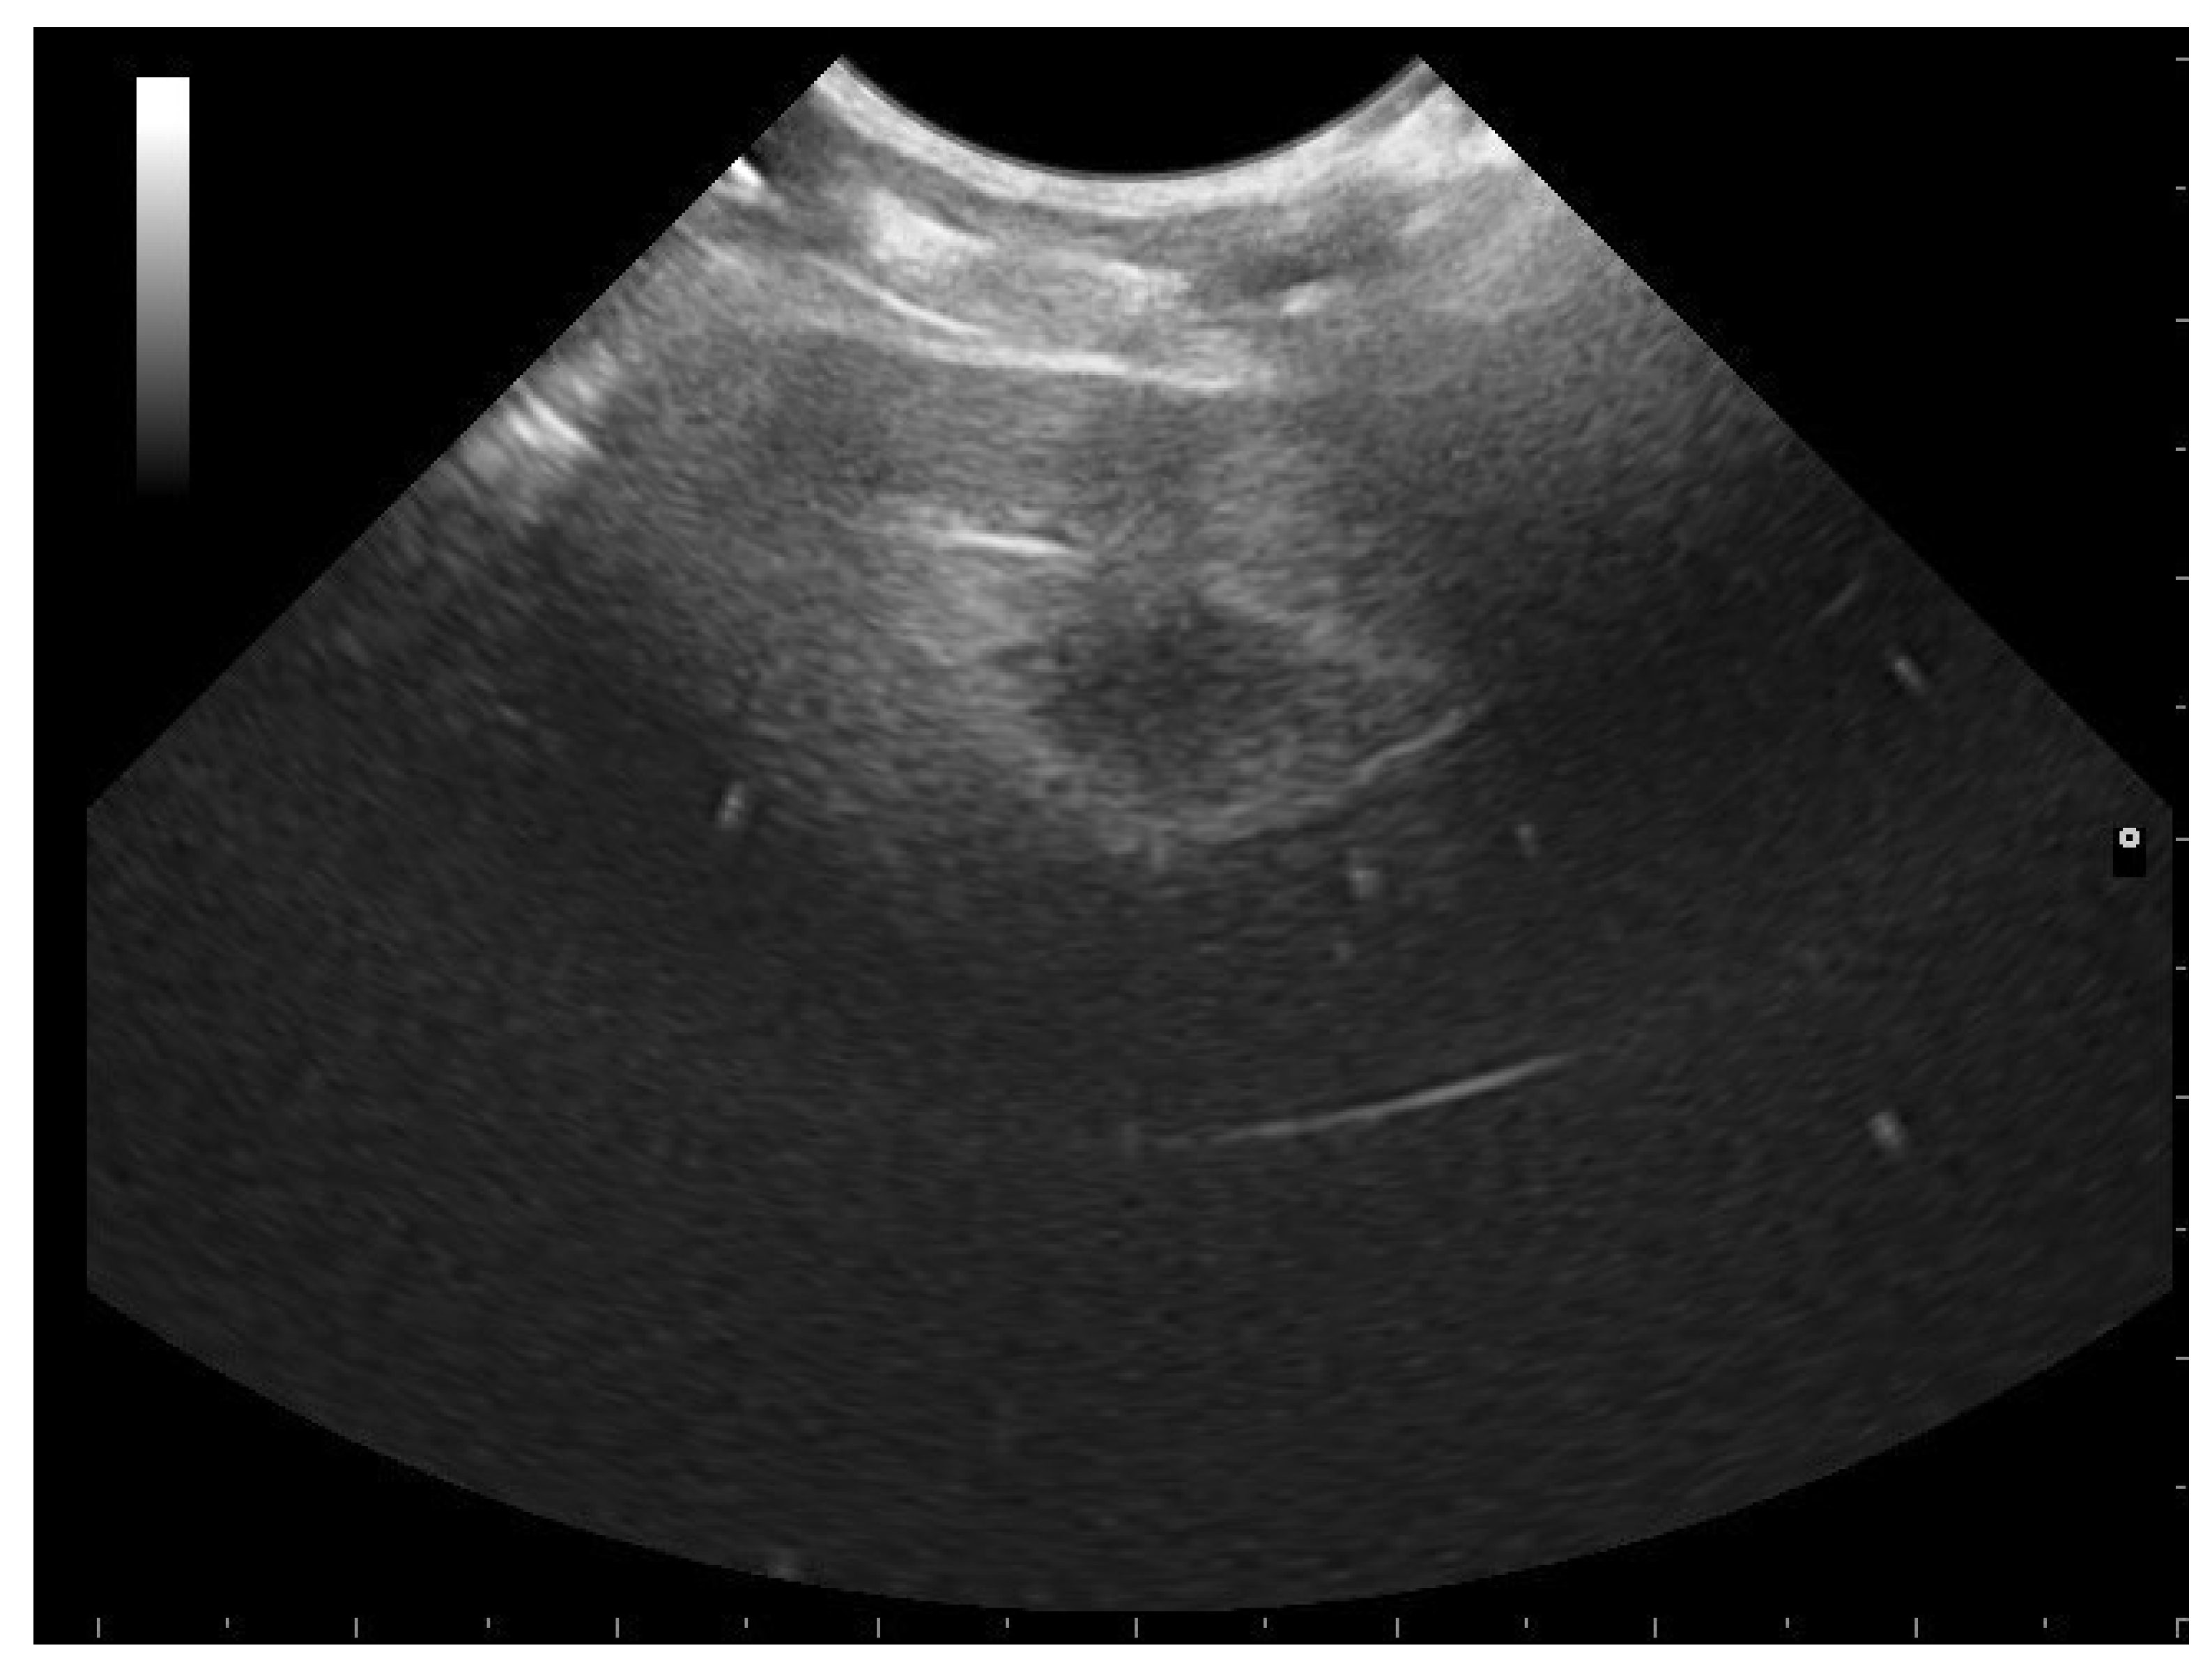

- Garcia, V.C.; Almeida-Santos, S.M. Reproductive cycles of neotropical boid snakes evaluated by ultrasound. Zoo Biol. 2021, 1–10. [Google Scholar] [CrossRef]

- Isaza, R.; Ackerman, N.; Jacobson, E.R. Ultrasound imaging of the coelomic structures in the Boa constrictor (Boa constrictor). Vet. Radiol. Ultrasound 1993, 34, 445–450. [Google Scholar] [CrossRef]